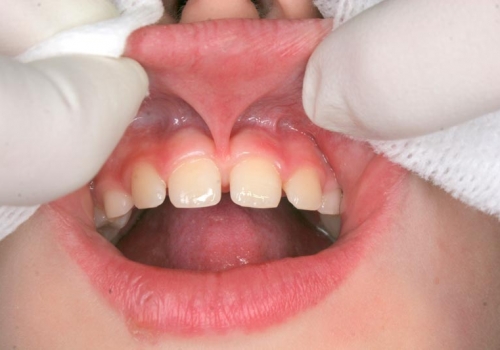

Frenulum (yüyən), diş əti toxuması (gingiva) ilə dil, dodaq və yanaq arasında yerləşən, toxumaları bir-birnə bağlayaraq hərəkətlərini sərhədləndirən yumuşaq selikli qişa toxumasıdır. Frenulum normal ölçülərdən böyük və qalın olduqda və ya diş əti kənarına yaxın yerləşdikdə bəzi narahatlıqlara və məhdudiyyətlətə səbəb ola bilir. Diş əti çəkilməsi, estetik məhdudiyyət, diastema, çıxan protez istifadə edən şəxslərdə protez fiksasiyasının məhdudlaşması və s. durumlar bununla bağlı ola bilir.

Sadalanan məhdudiyyətlərin ortadan qaldırılması və ya önünə keçilməsi məqsədilə frenulumun tamamən uzaqlaşdırılması (frenektomiya) həyata keçirilir. Bu prosedur həm ənənəvi cərrahi həm də lazer cərrahiyyəsi metodu ilə aparılır. Hansı metodun tətbiq edilməsi hər bir kliniki halda fərdi şəkildə qərara alınır.